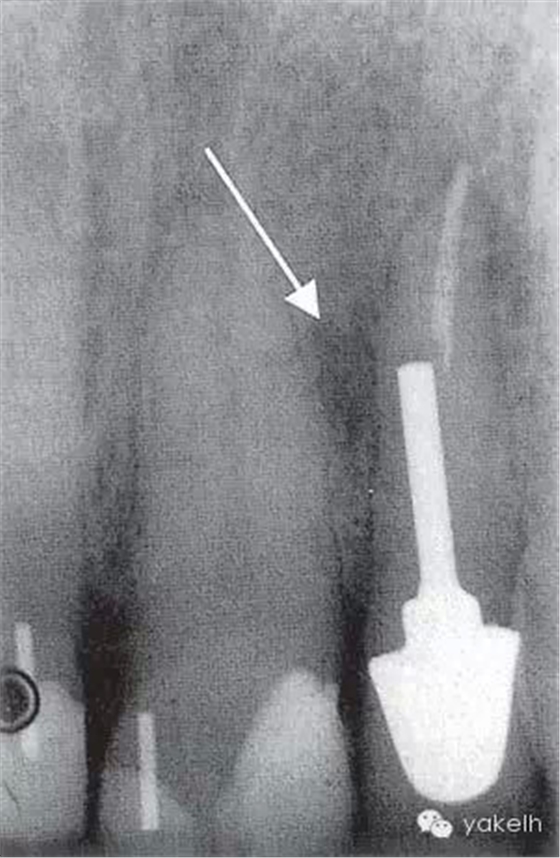

¤¤口外檢查可見顳下頜關(guān)節(jié)處輕微捻發(fā)音,開口度、開口型正常,無疼痛,未見其他異常??趦?nèi)檢查可見牙列中有部分良好的修復(fù)體,無齲壞;局部牙齦炎,探診出血,牙周探診深度不超過2mm。22唇側(cè)牙槽黏膜可見竇道(圖5.4.1a),輕微叩痛,竇道區(qū)捫痛,根尖X線片顯示牙根中部透射影,疑為樁穿孔(圖5.4.1b)。左上頜中切牙(21)和左上頜尖牙(23)對EPT和冷測試反應(yīng)正常。

圖 5.4.1(b)22根尖X線片,顯示樁穿孔側(cè)方的根周透射影。